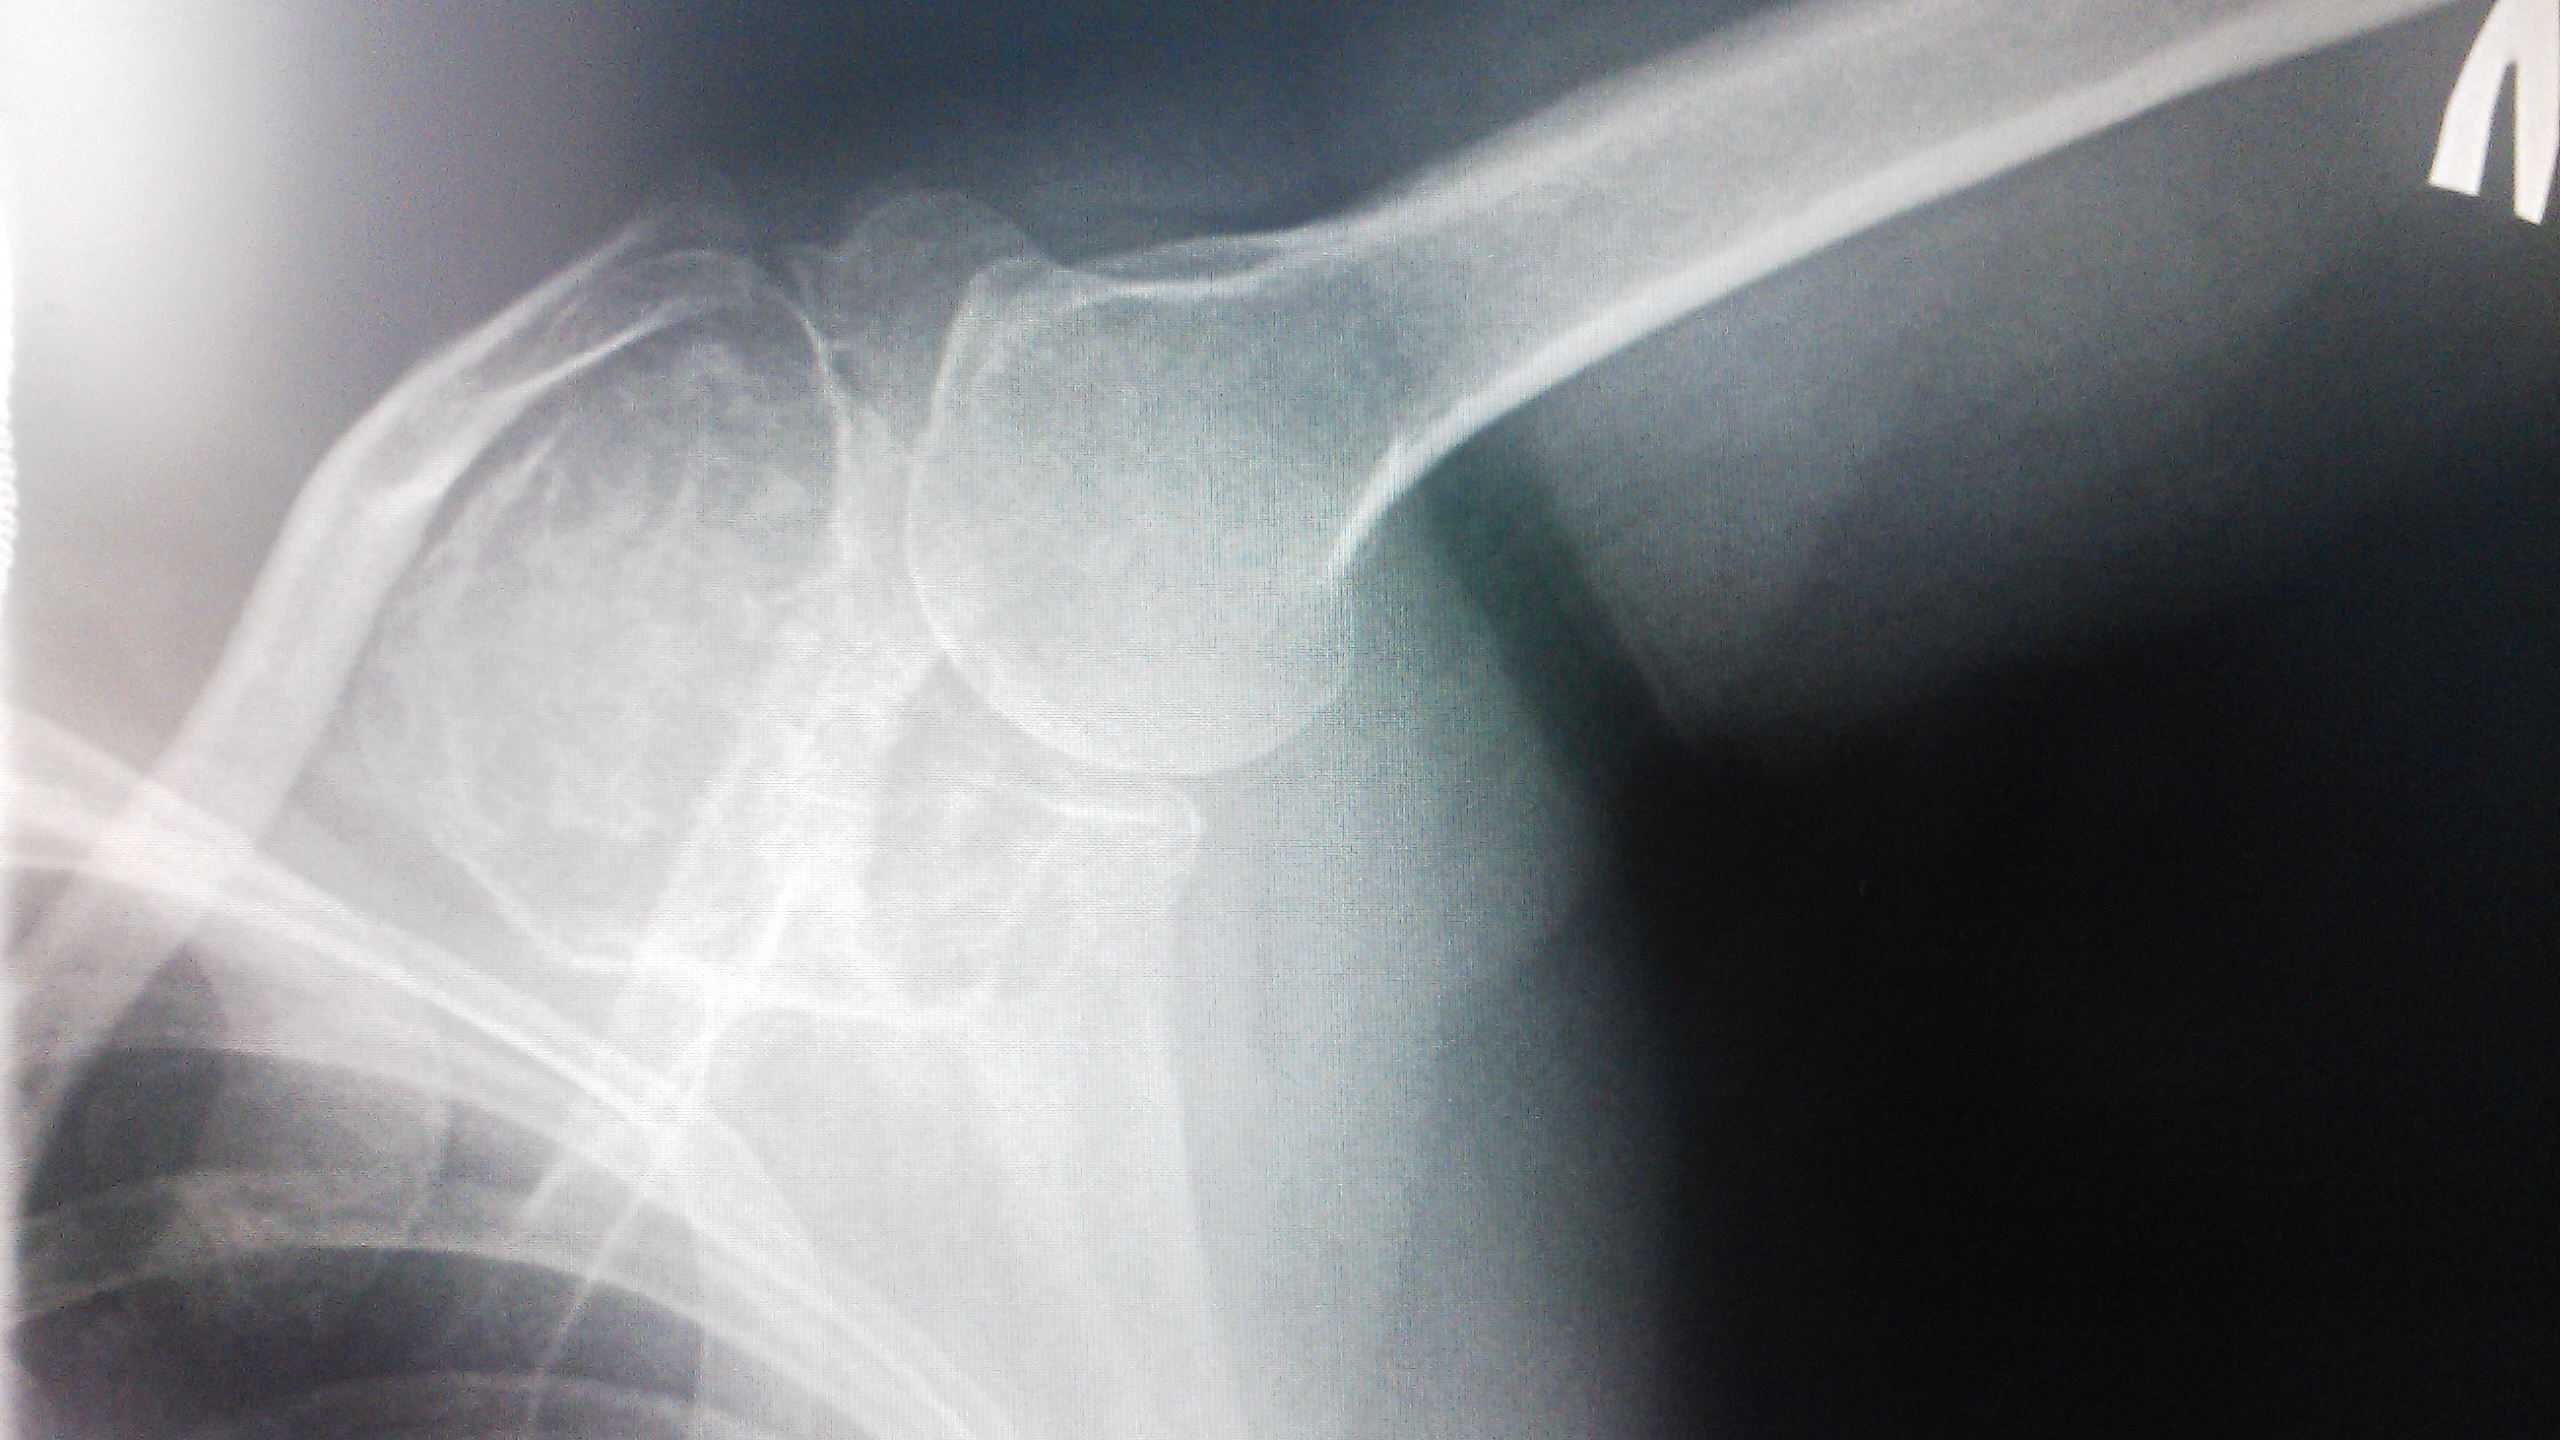

Рентгеновские снимки анкилоза суставов: Как это выглядит